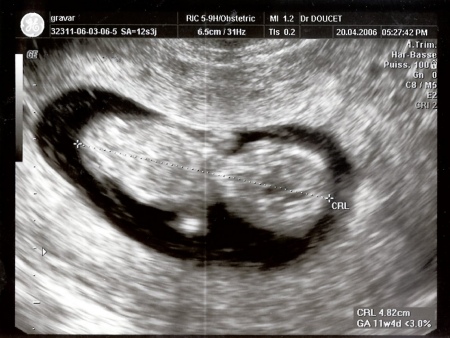

20 avril 2006

A l'intérieur, je ressemble à ceci :